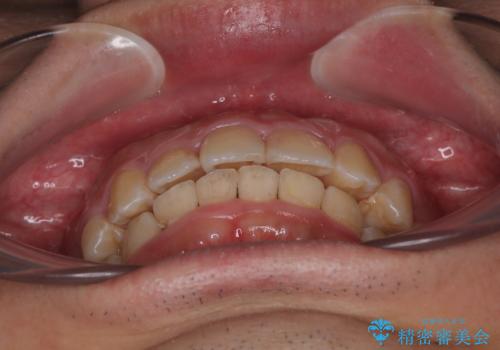

- デコボコと奥歯の咬み合わせのズレを気にして来院された患者様です。

骨格的に、下顎が右側にずれており、左側の咬み合わせに鋏状咬合などのアンバランスが生じている状態でした。

また、上顎前歯に欠損が1本あり、上下ともに前歯部に叢生が認められ、下顎前歯の大半が隠れてしまうほどの過蓋咬合も認められました。

咬合平面を平坦にしながら前歯の咬み合わせを挙上し、デコボコと鋏状咬合も改善していくこととしました。